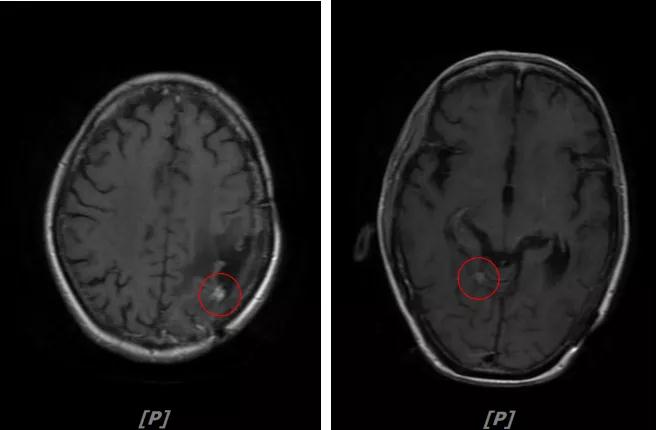

5. 病情第4次进展:2019年11月患者出现视野模糊等症状

头颅增强MR:左侧顶颞叶见片状T1WI低信号、T2WI高信号影,病灶大部信号接近脑脊液,增强后术区边缘左侧顶叶见结节状强化影,大小约10x8x11mm,较2019-03- 15MR老片大致相仿;右侧脑室三角区见结节样T1WI等低信号、T2WI不均匀稍高信号影,增强后不均匀明显强化,大小约24x18x20mm,较2019-03-15MR老片明显增大;两侧半卵圆区、侧脑室旁见较对称片状T1WI低信号、T2WI高信号影,增强后未见明显强化,较前片相仿;余脑室、脑池、脑沟大小形态可,中线结构向左偏移。

左顶颞叶转移瘤治疗后改变

右侧脑室三角区旁强化结节,较2019-03-15MR老片明显增大 左侧顶叶强化结节,较2019-03-15MR老片大致相仿

两侧脑室旁云絮状异常信号,考虑放疗后改变